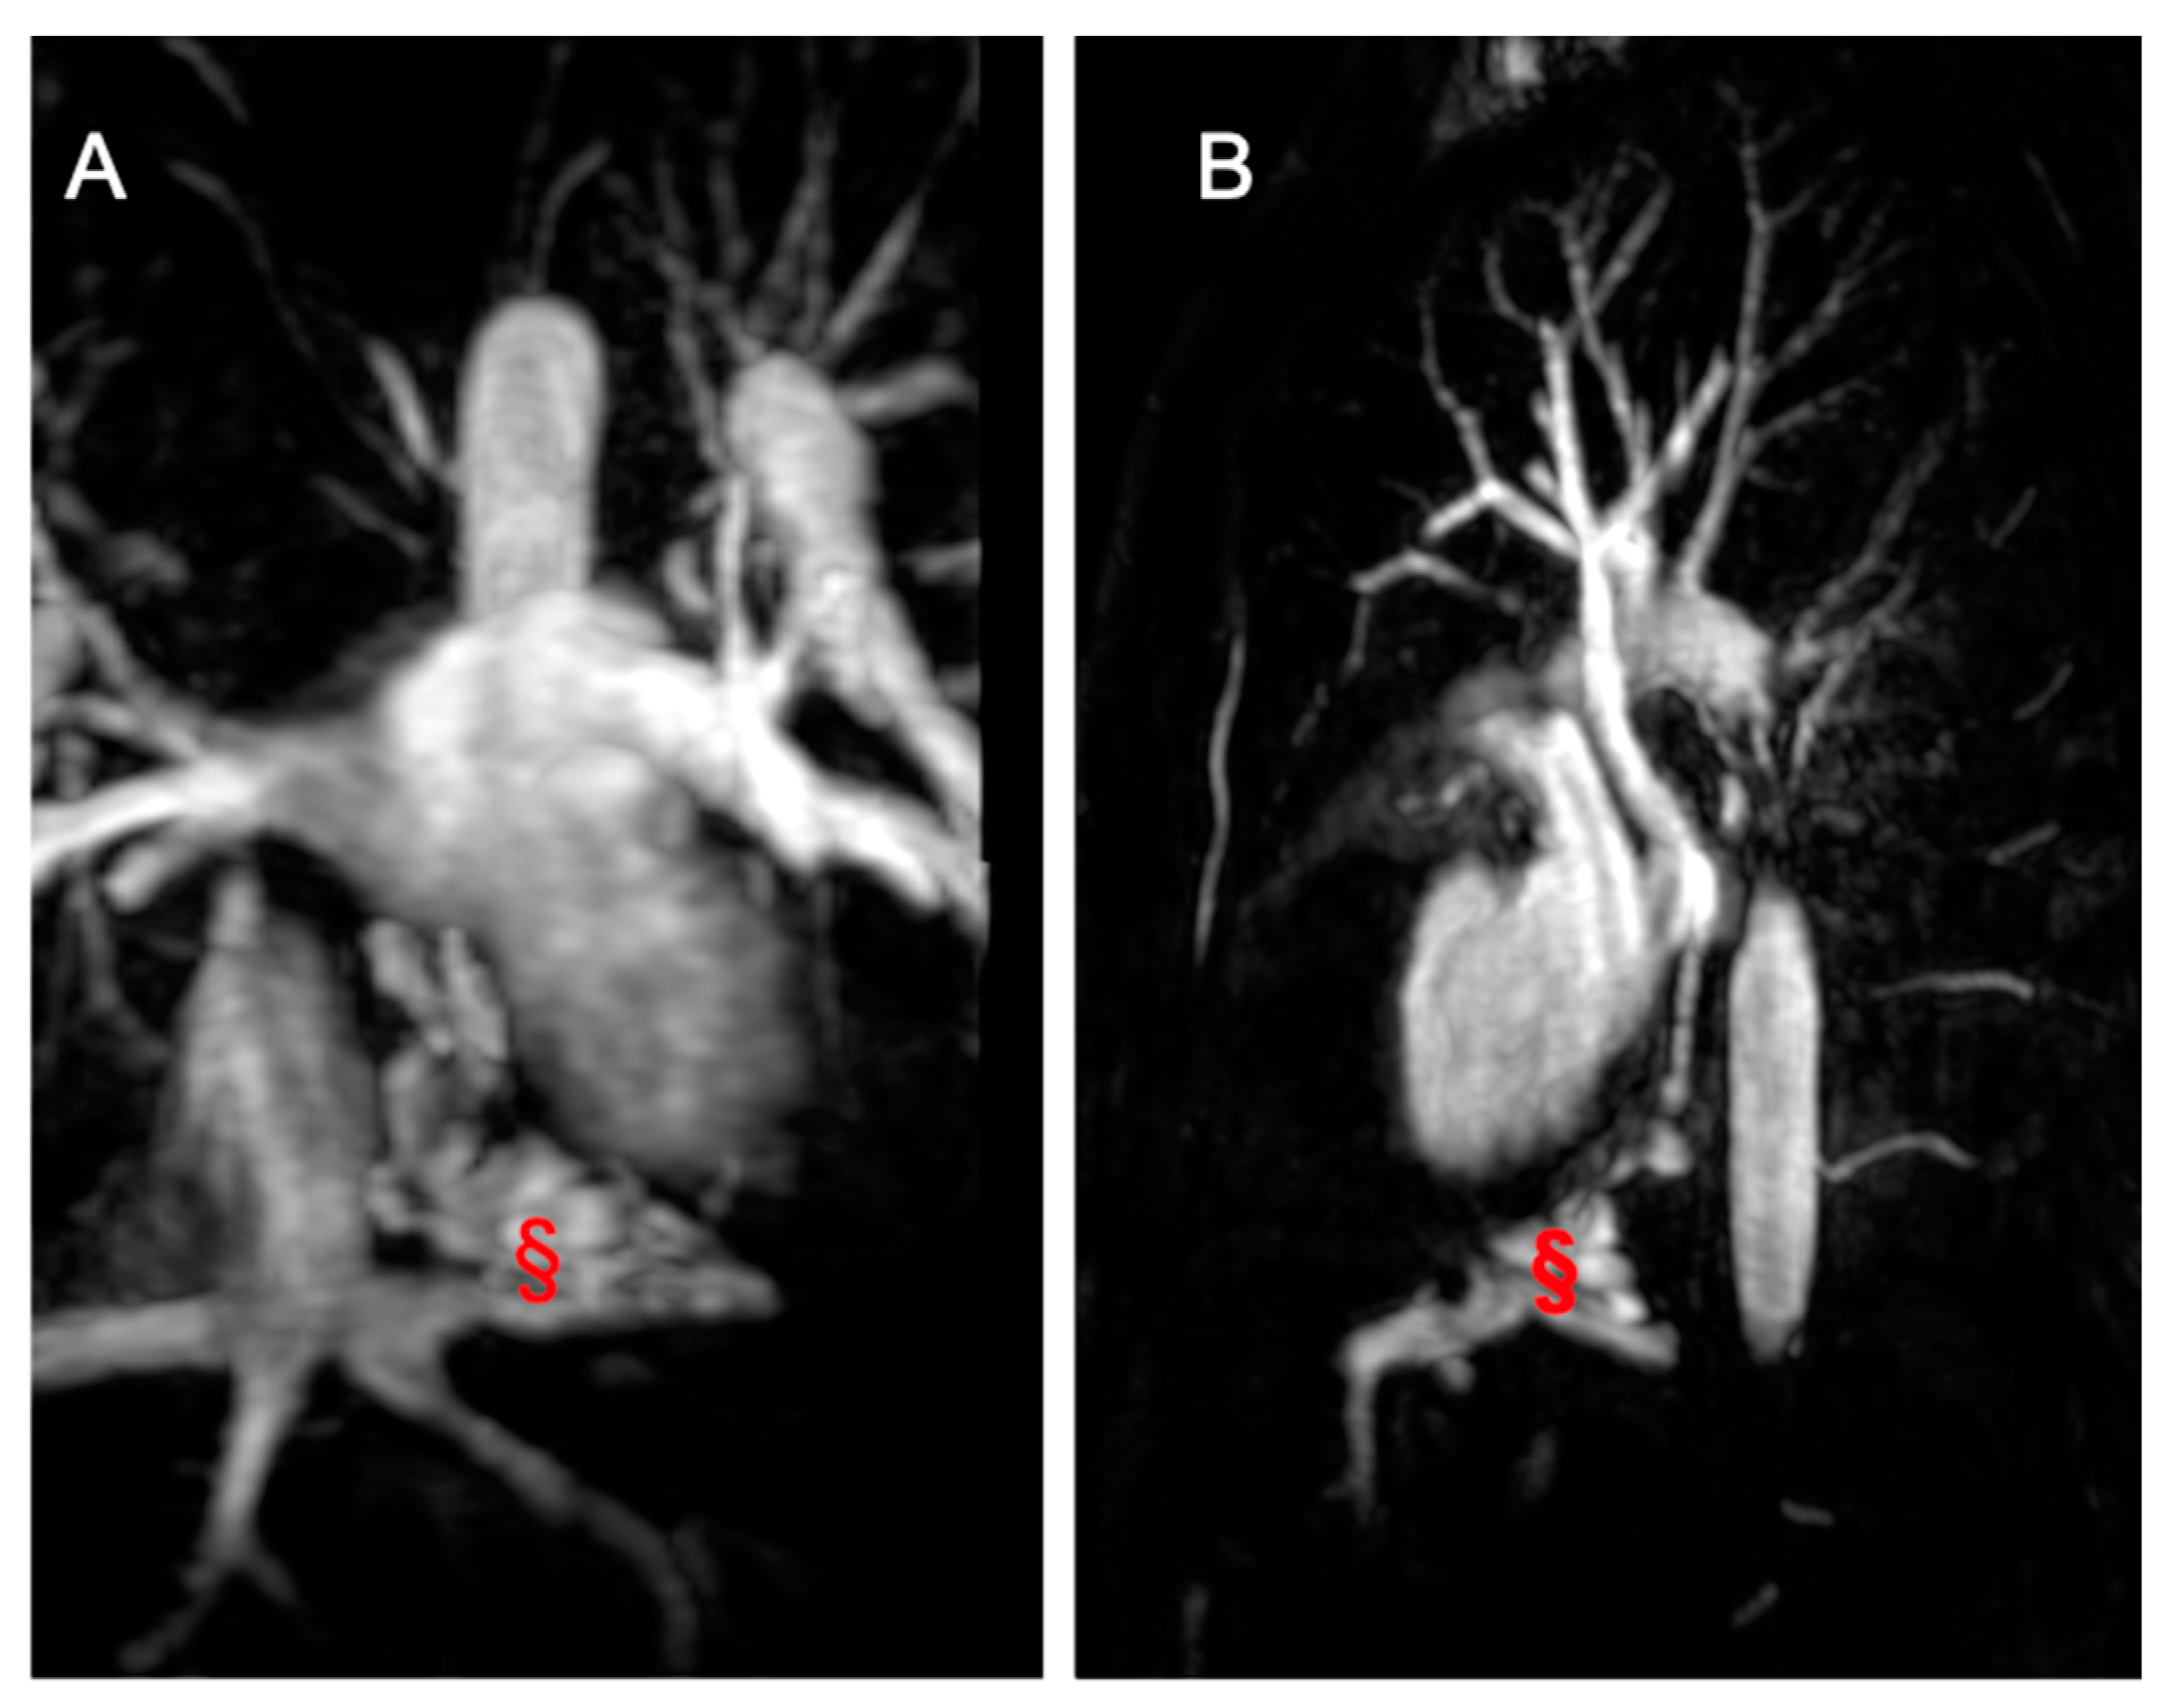

Figure 8.

Imaging from a 17-year-old male TCPC. (A) shows a coronal angiography image, while (B) presents a sagittal angiography image displaying a veno-venous fistula (marked with §) between the suprahepatic veins and the pulmonary veins.